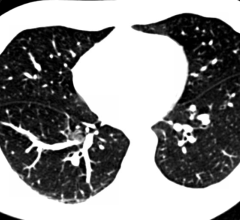

Computed tomography (CT) has evolved significantly since its debut in the 1970s. While the basic principles have stayed the same, manufacturers have been able to expand on these principles to offer enhanced performance and image quality, as ITN contributing editor Greg Freiherr discovered during the 2015 Radiological Society of North America (RSNA) annual meeting, Nov. 29-Dec. 3 in Chicago.